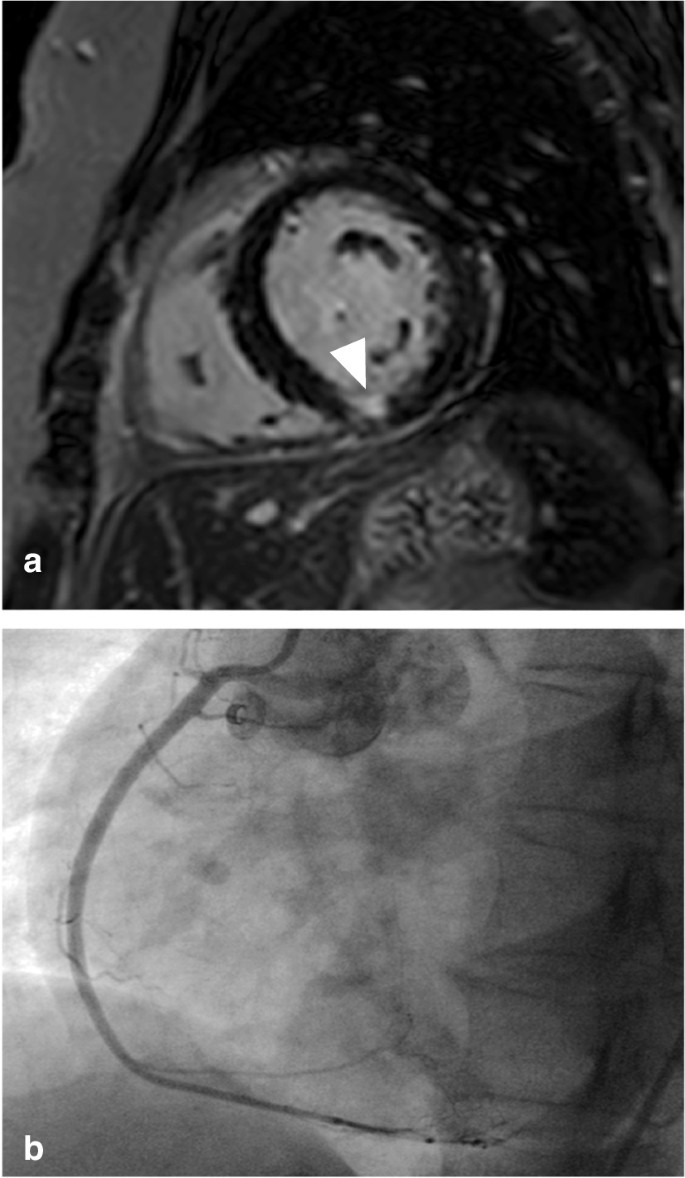

Combined cine, T2-weighted and LGE-CMR imaging (step 1) was evaluated in all 51 patients and suggested a coronary etiology in 32 (63%; Fig. 1). The sensitivity, specificity and overall accuracy to detect obstructive CAD were 79% (95%CI 62–91%), 71% (95%CI 44–90%) and 77% (95%CI 63–87%), respectively (Table 3). In 19 (37%) patients, the scan was either normal or equivocal and adenosine stress-perfusion imaging was added as a second step (Fig. 1). In this cohort, adenosine stress-perfusion imaging (step 2) had a sensitivity, specificity and overall accuracy of 86% (95%CI 42–100%), 92% (95%CI 62–100%) and 90% (95%CI 67–99%), respectively to detect obstructive CAD. When the results of both steps were combined, obstructive CAD was correctly identified in 33 of 34 patients (sensitivity 97% (95%CI 85–100%)). A coronary etiology was suggested by CMR in 6 out of the 17 patients (35%) with non-obstructive CAD, leading to a specificity of 65% (95%CI 38–86%). Overall accuracy remained high at 86% (95%CI 74–94%). After removing T2-weighted imaging from the initial combination of cine and LGE in step 1, followed by adenosine stress-perfusion imaging (step 2), sensitivity remained high at 94% (95%CI 80–99%), with a specificity of 65% (95%CI 38–86%) and accuracy of 84% (95%CI 71–93%). Patient examples are shown in Figs. 2, 3, 4.

Patient example. Upper row: basal-inferior-inferoseptal edema on T2-weighted short axis left ventricular image (a arrowheads), 50–75% transmural basal-inferior-inferoseptal myocardial infarction with microvascular obstruction (b arrowheads). Lower row: total occlusion of the mid right coronary artery (c arrowhead), 71–90% mid left anterior descending artery stenosis (d arrowhead) with collaterals to right coronary artery (d asterisk)